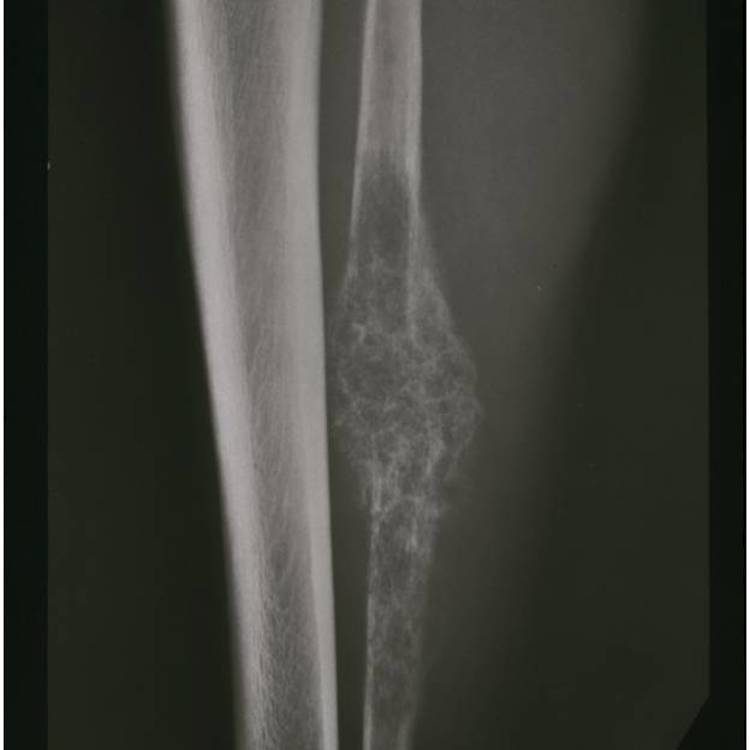

Radiographic imaging is used to help form a diagnosis. These include X-Ray, MRI, CT and Bone Scans.

An example of an Mesenchymal Chondrosarcoma MRI is shown.